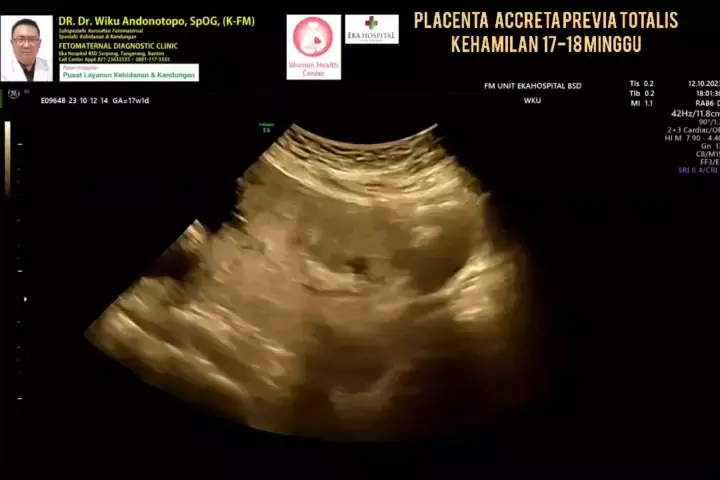

Plasenta Previa Totalis Accreta.... #drwikuandonotopo #drwiku_andonotopo #polikandunganekahospitalbsd #fetomaternalekahospitalbsd #usgfetomaternalekahospitalbsd #konsultanfetomaternalekahospitalbsd #ekahospitalbsd #ekahospitalcibubur #ekahospitalbekasi #ekahospitalpekanbaru #fetomaternalbekasi #fetomaternalcibubur #fetomaternal #konsultanfetomaternal #usg #usg4d #perkembanganbayi #perkembanganjanin # #melahirkannyaman #melahirkannormal #melahirkancesar #janin #lahiran #melahirkan #melahirkan...